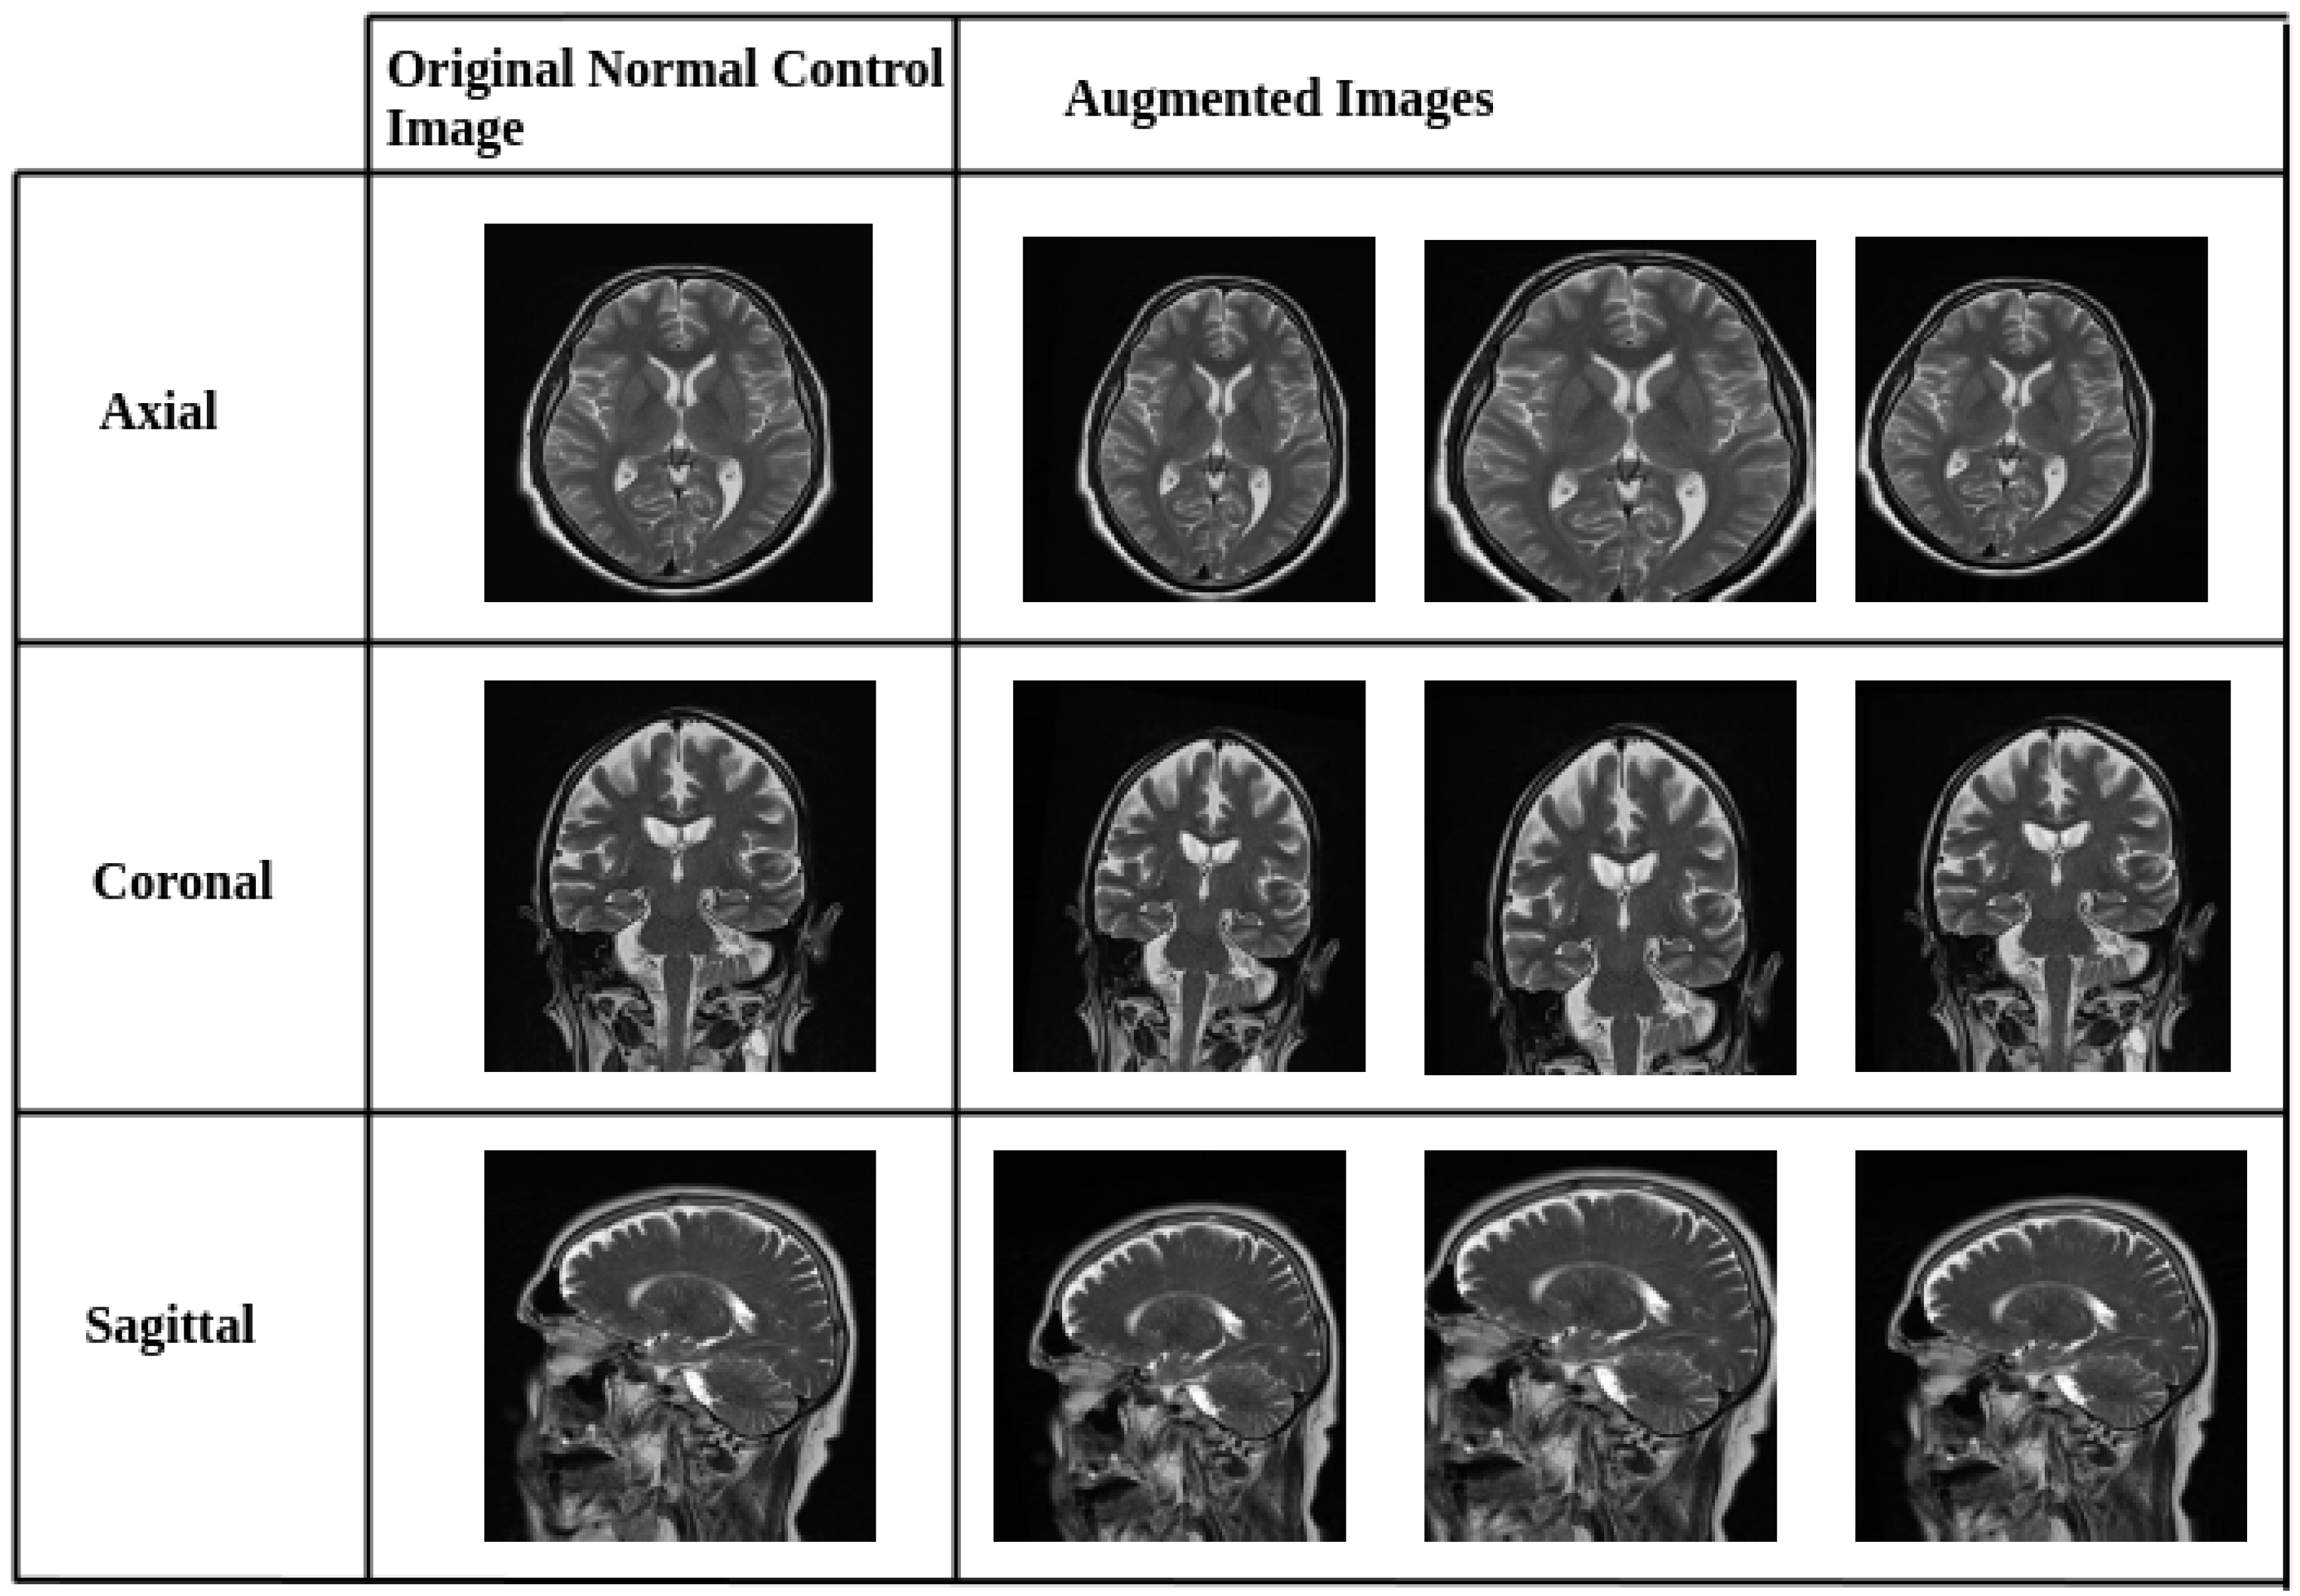

To mitigate class imbalance between Alzheimer’s disease (AD) and normal control (NC) images in the AlzaSet dataset, we applied partial data augmentation exclusively to the underrepresented NC cohort. Geometric transformations, including 5% horizontal and vertical translations, 5° rotations, and 0.05× zoom scaling, were employed to synthetically expand the NC subset and approximate numerical parity with AD cases. Representative augmented images from the NC group are illustrated in Figure 1.

Figure 1.

Representative Data Augmentation Pipeline for Normal Control (NC) Class. Sample images from the NC cohort after applying geometric data augmentation techniques. Transformations include horizontal and vertical shifts (±5%), 5-degree rotations, and 0.05× zoom scaling. These augmentations were applied to address class imbalance by synthetically expanding the NC dataset, thereby improving model generalization and reducing overfitting.